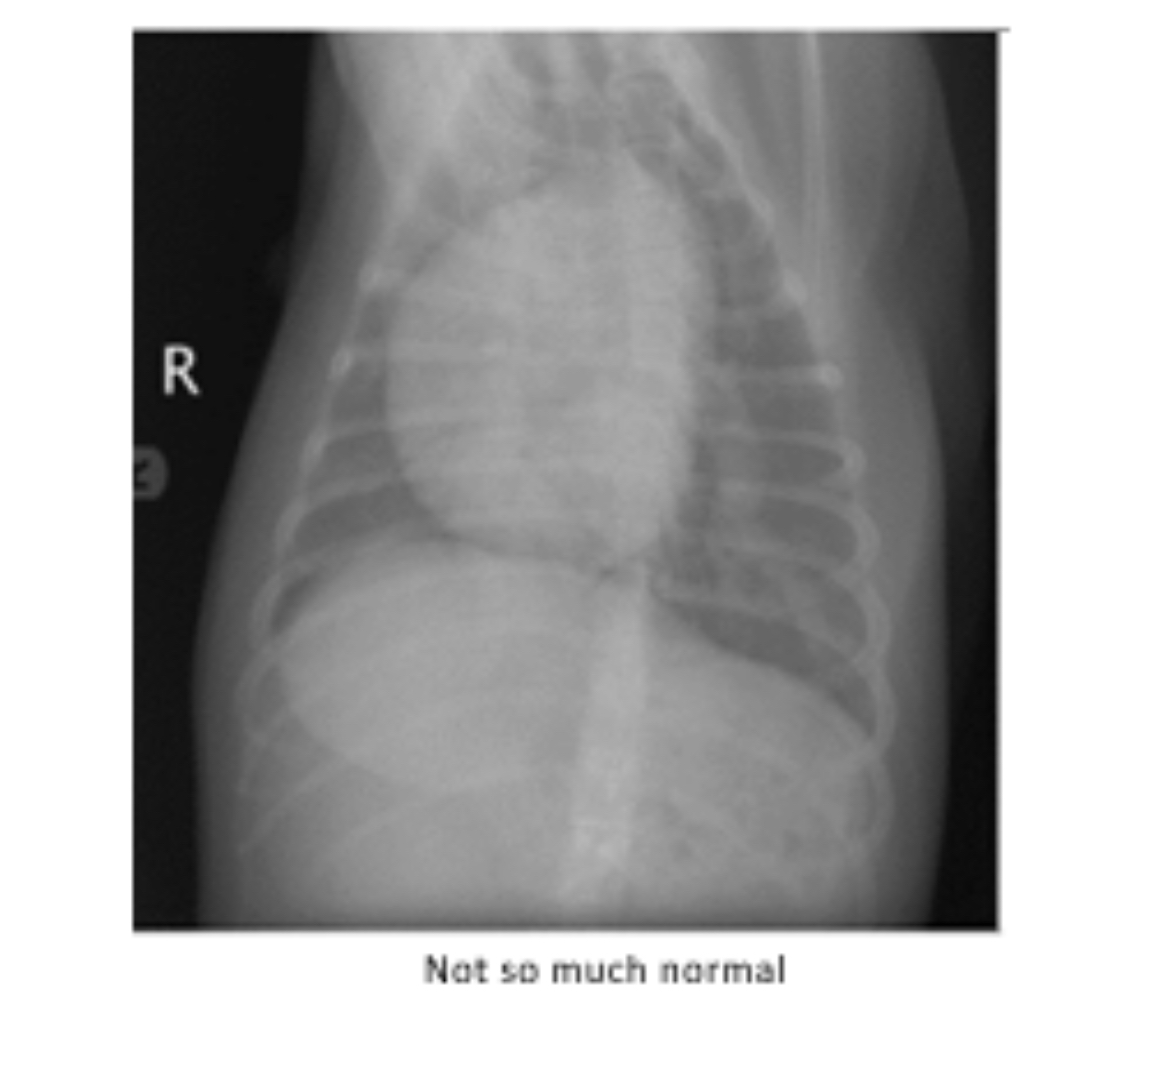

Examine this normal canine chest radiograph compared to Midnight's abnormal one. Which side of the heart appears enlarged?

Right

This diagram illustrates what's happening in the abnormal radiograph. In dogs, adult heartworms take up residence in which chamber of the heart and which blood vessel (as indicated)?

Chamber: __________ (Blank 1)

Blood vessel: ___________ (Blank 2)

#1: right ventricle

#2: pulmonary artery

This infliction may lead to pulmonic stenosis (narrowing) of the outflow of the blood vessel listed above/in the previous question.